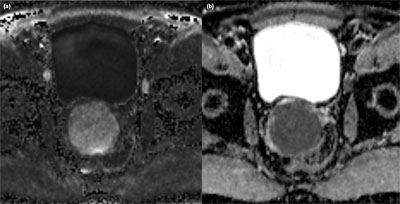

Figure 2

a) (b1400) and b) (ADC). The lesion has restricted diffusion on transverse high b-value image, corresponding to an ADC of 0.791 ×10–3 mm2/s.